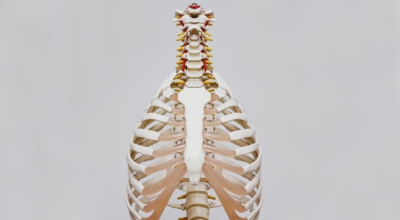

갈비뼈란?

흉추와 복장뼈를 관련해서 가슴 전체를 둘러싸고 있는 가슴우리(흉강)을 형성하는 긴 곡선의 뼈를 말합니다. 갈비뼈는 폐, 심장 등 내부 가슴 장기들을 지켜주며 가슴우리의 팽창과 수축으로 호흡을 도와줍니다. 우리 몸은 총 12쌍의 갈비뼈를 가지고 있답니다.

1~7번 갈비뼈는 복장뼈와 직접 관절로 연결되어 있어 참갈비뼈라고 하며, 8~12번 갈비뼈는 거짓 갈비뼈라고 하는데 거짓 갈비뼈 중 8, 9, 10번 갈비뼈는 또다른 연골을 통해 복장뼈와 연결되어 있으며 나머지 11~12번째 갈비뼈는 뜬갈비뼈로 복장뼈와 연결되어 있지 않습니다.